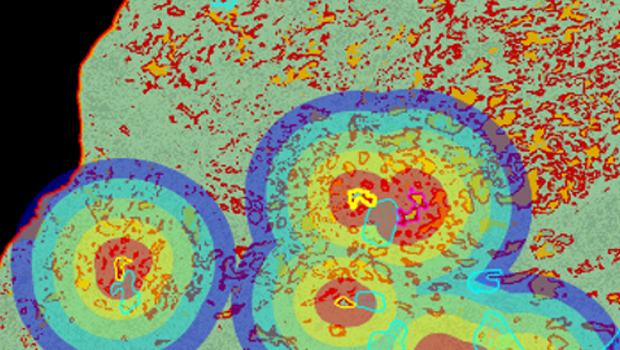

空间浸润分析用于分析病灶区域(如肿瘤、坏死、纤维化等)周围某类细胞的浸润情况。如常用于肿瘤免疫浸润分析。